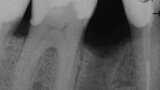

3D technologie v diagnostice a léčbě endodontických onemocnění